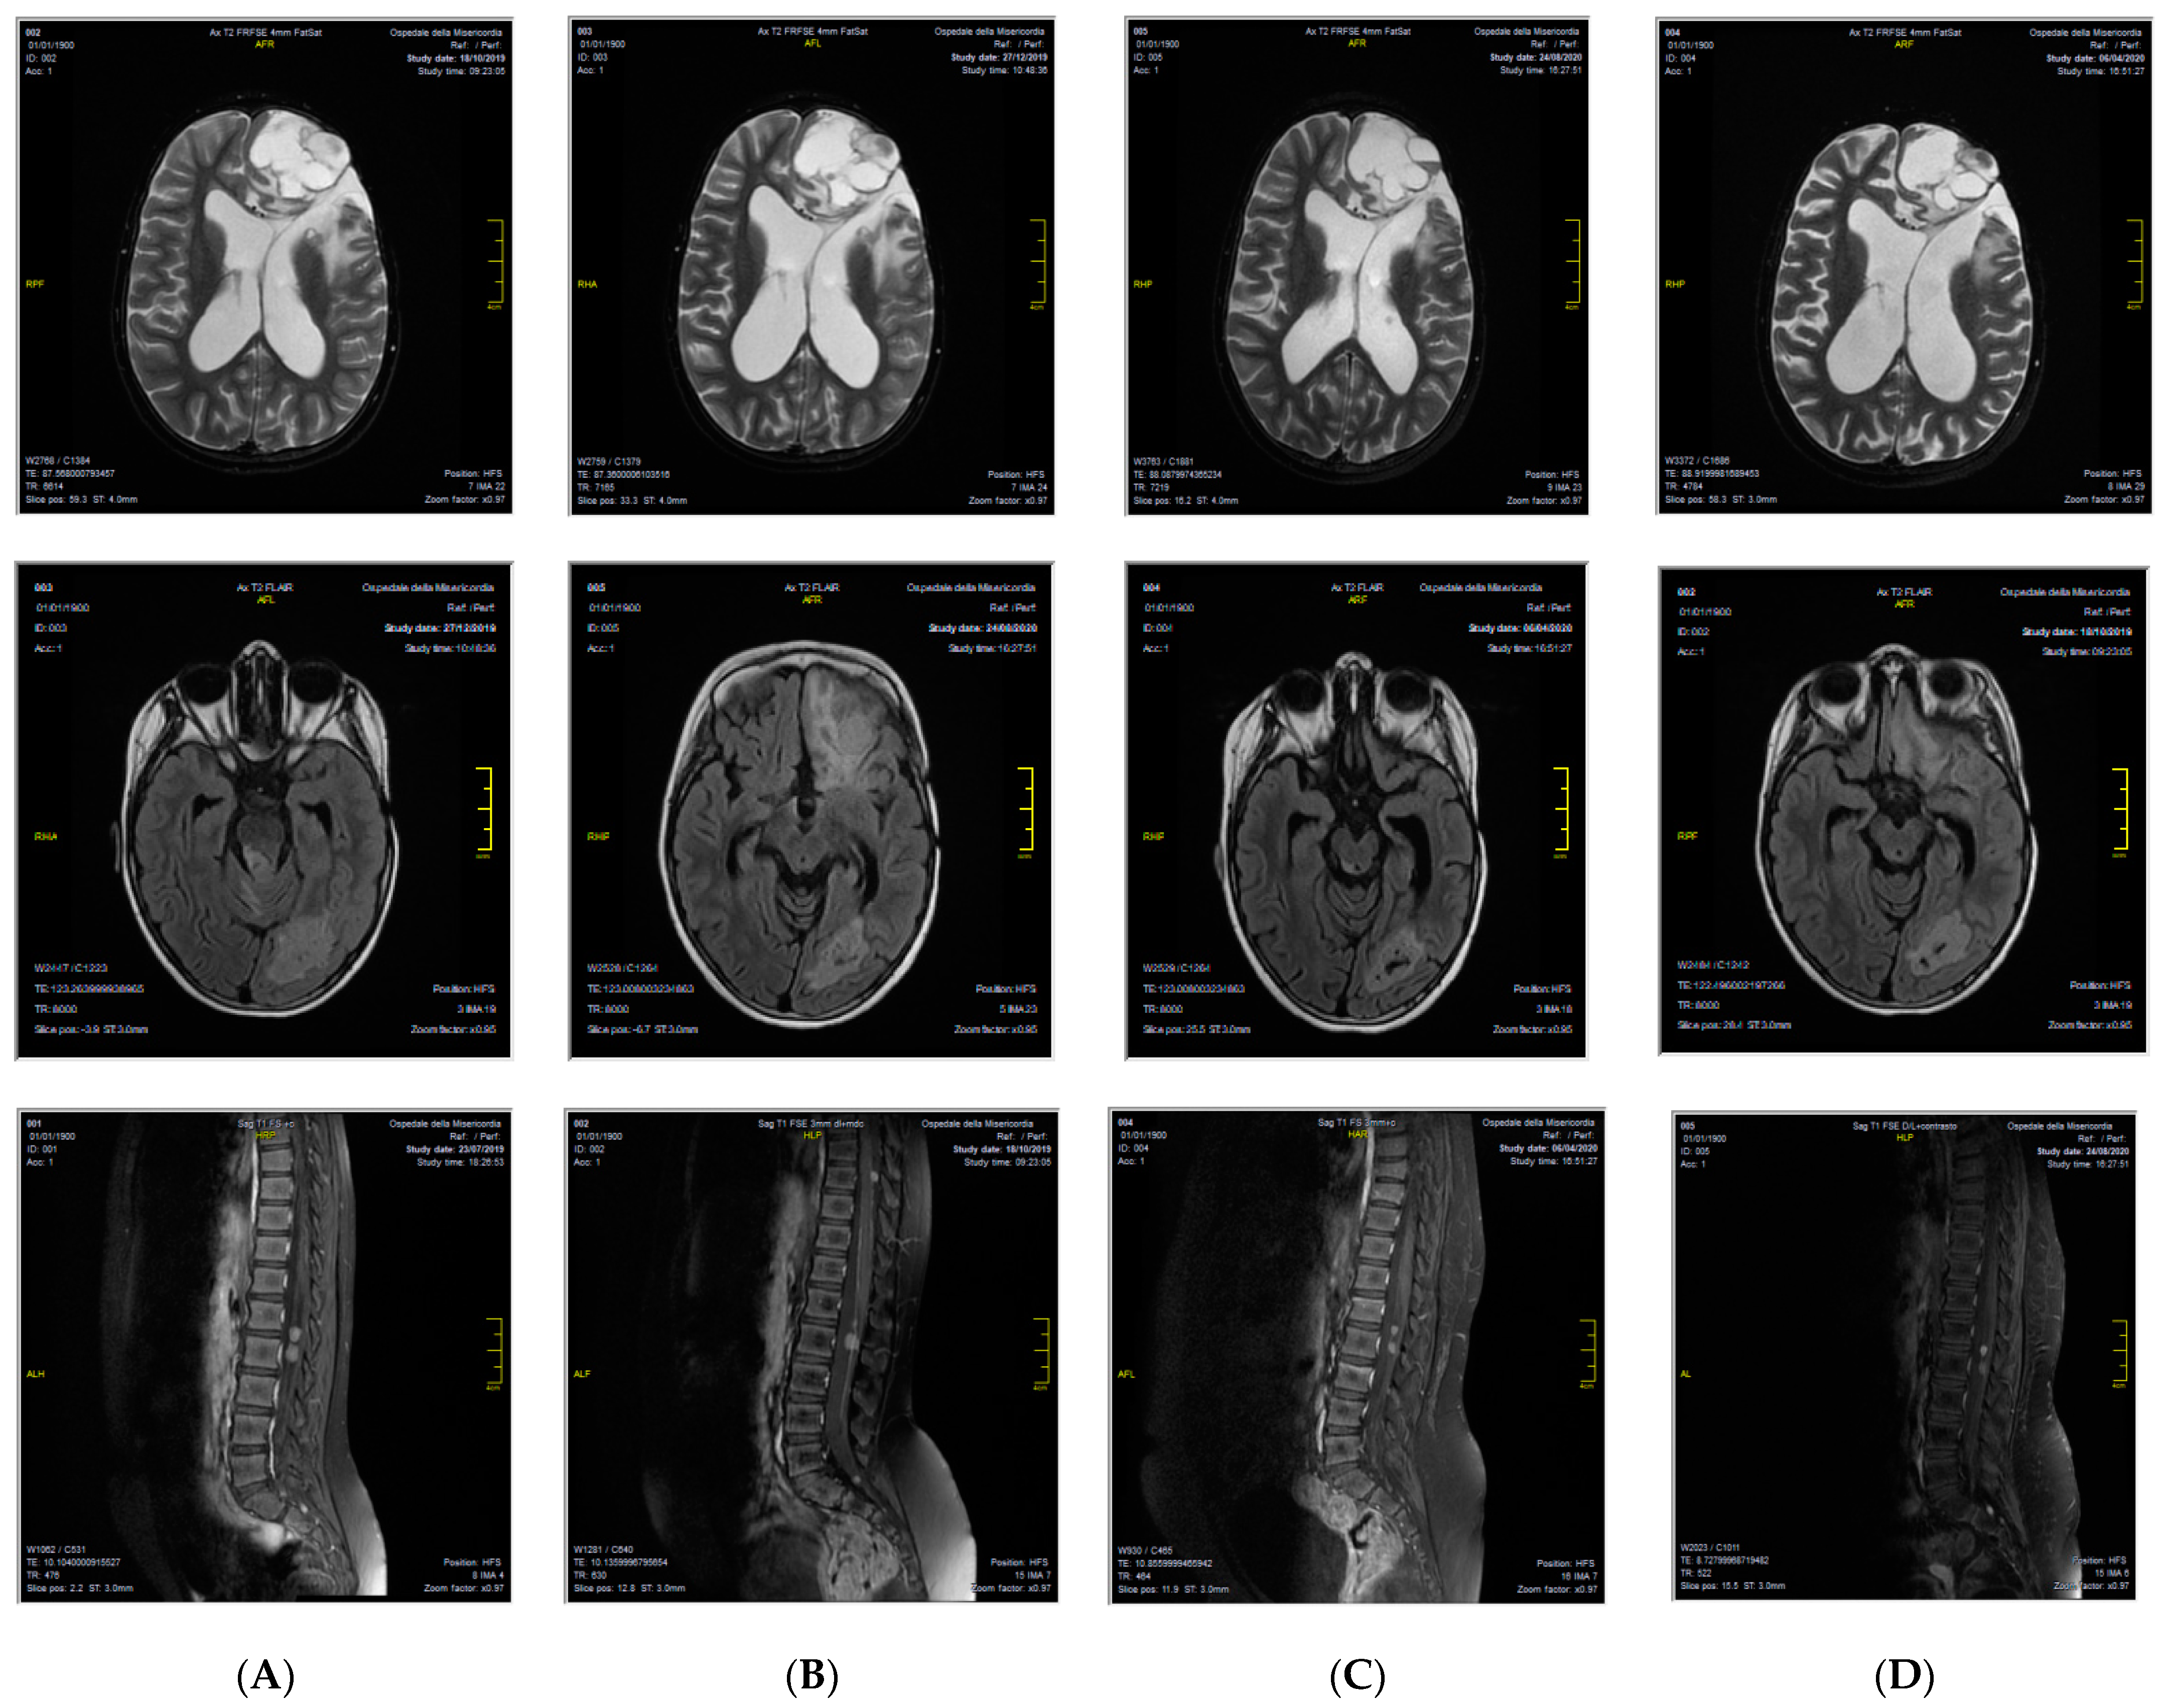

A 7-year-old female patient from Morocco came to our attention with a diagnosis of relapsed grade III EPN 4 years from the primary diagnosis, which was made in her origin country, done after seizure appearance. The tumor was localized in the left frontal lobe and was completely removed by surgery. From December 2016 to February 2017, the child received three courses of adjuvant chemotherapy with cisplatin and etoposide. In March 2017, a relapse occurred in the primary tumor site. It was treated with surgery and three courses of chemotherapy with ifosfamide and etoposide. Complete remission was obtained. In October 2017, a second relapse occurred again in the left frontal lobe, which was treated with surgery and radiotherapy (59.4 Gy). Complete remission was achieved. In April 2019, a third relapse was diagnosed, and the patient was considered incurable in her origin country. For this reason, she was referred to our Center, where a full CNS magnetic resonance imaging (MRI) evaluation documented a multifocal disease both in the brain and in the spinal cord. CNS fluid analysis was negative for leptomeningeal dissemination. We decided to treat her with oral etoposide and dexamethasone. A follow-up MRI done in October 2019 showed a disease progression, but clinical conditions were still good, and we did not modify the current treatment. In December 2019, the patient was admitted to the hospital due to worsening general clinical conditions, which moved rapidly to a comatose state. We administered anti-edema treatment with high-dose dexamethasone and 20% mannitol, with an improvement of the clinical feature. The MRI showed an ulterior disease progression. For this reason, we decided to substitute etoposide with temozolomide. In January 2020, the patient was again admitted to the hospital because of neurological symptoms (headache, vomiting, and hyposthenia of the right part of the body); anti-edema treatment was done and then radiotherapy on the left frontal lesion. We obtained histological material from the last surgery done in her origin country. Diagnoses of anaplastic ependymoma with RELA gene expression were confirmed. The immune phenotype analyses on paraffine tumor sample revealed: p65+, LICAM+, OLIG2-, p53+, GFAP+, EMA+, Synaptophysine+, ATRX+, m-TOR+, PD-L1+ (20%), and PD-1-. Based on these findings, in February 2020, we decided to start targeted therapy with orally dispensed sirolimus 2 mg/Kg/day every day and IV nivolumab 3 mg/Kg every 2 weeks. Sirolimus dosage was modulated on patient plasmatic concentration. Local Ethics Committee approved the nivolumab off-label use, and written informed consent was signed by the parents, according to the Declaration of Helsinki. Treatment was continued for 1 year until disease progression. During this period, the patient experienced a varicella-zoster virus (VZV) infection, which required IV acyclovir, and dexamethasone was definitively withdrawn (July 2020). In April and August of 2020, control MRI showed substantially stable disease in both the brain and the spinal cord (Figure 1). At one-year follow-up, the patient had disease progression; however, her current clinical conditions are good and neurological assessment completely negative.

Figure 1. CNS MRI patient evaluation during therapy with nivolumab and sirolimus, showing a substantially stable disease in the brain and in the spinal cord at different time points. (A) January 2020; (B) April 2020; (C) August 2020; (D) January 2021.